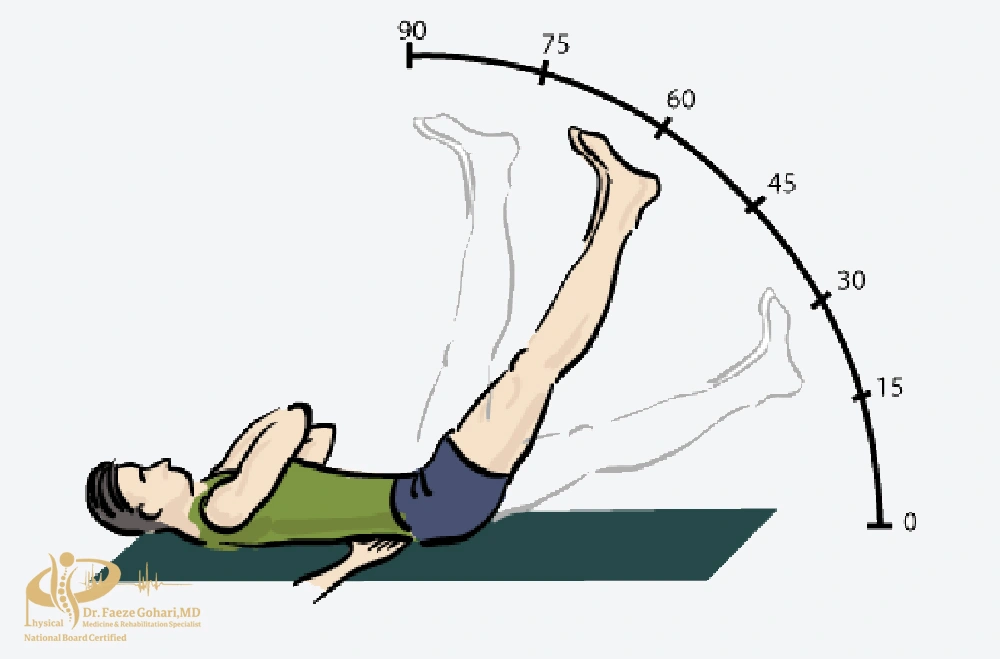

بالابردن پای صاف

به پشت بخوابید، یکی از پاها را با زانوی صاف تا زاویه ۴۵ درجه بالا بیاورید و ۳ ثانیه نگه دارید، سپس بهآرامی پایین بیاورید. این تمرین عضلات اطراف زانو را بدون آسیب تقویت میکند.